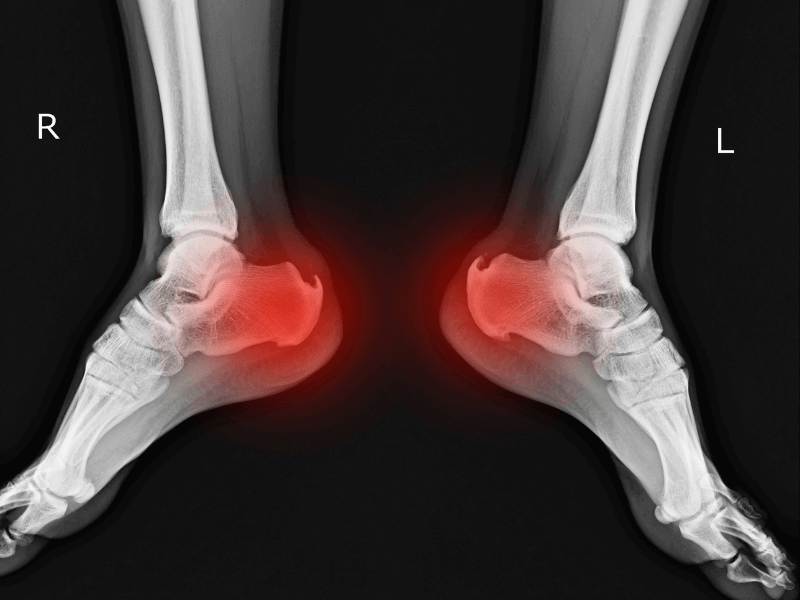

Gai gót chân là tình trạng canxi lắng đọng tạo thành gai xương ở mặt dưới xương gót. Gai này chèn ép mô mềm, dây chằng quanh gót chân, gây đau nhức, đặc biệt khi đứng lâu, vận động nhiều hoặc bước đi buổi sáng.